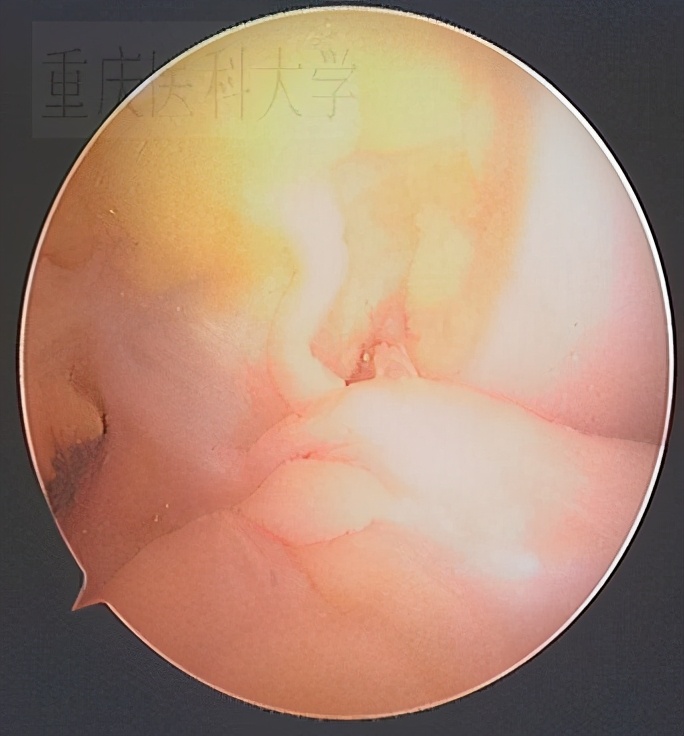

膝关节韧带损伤治疗主要手段是关节镜治疗:关节镜检后获得明确诊断,然后制定治疗方案:半月板缝合或成形,交叉韧带重建、撕脱骨折复位固定等。

重建术前的 前交叉韧带 :

单束重建术后的前交叉韧带: